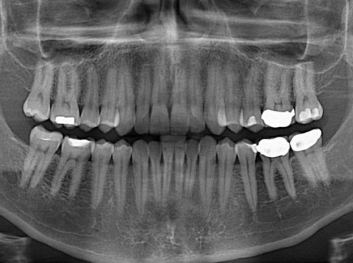

損壞的牙齒如何自我修復(fù)?近日,來自哈佛大學(xué)和諾丁漢大學(xué)的研究人員研發(fā)了能夠刺激牙齒干細(xì)胞再生的新型生物材料,而這種新材料研發(fā)成功的背后,正源于他們對(duì)牙齒如何實(shí)現(xiàn)自我修復(fù)這個(gè)課題的不斷探索。

據(jù)美國(guó)期刊《大眾科學(xué)(Popular Science)》報(bào)道,此種新型生物材料,不僅可以有效地取代傳統(tǒng)補(bǔ)牙填充物,刺激牙齒干細(xì)胞再生,患者也有望無需再接受根管治療,使蛀牙患者免除牙根感染或牙髓壞死的苦惱,一個(gè)全新的牙齒治療時(shí)代即將來臨。

Adam Celiz,是來自諾丁漢大學(xué)的研究人員,他和同事開發(fā)的這種新型合成生物材料,能刺激干細(xì)胞在牙髓部的生長(zhǎng)。與普通材料一樣,這種合成材料被填充到牙齒并用UV光硬化。

在體外測(cè)試中,材料刺激干細(xì)胞進(jìn)入牙本質(zhì)的增殖和分化速度,促進(jìn)形成牙齒骨組織。研究人員認(rèn)為,一旦材料在受損牙齒中應(yīng)用,這些干細(xì)胞可以自動(dòng)修復(fù)來自填充物上的損壞。在本質(zhì)上,該生物材料將使牙齒自愈。

在未來,Adam Celiz說,可再生材料能制成各種填充物以便受損牙齒的自身治愈,降低補(bǔ)牙失敗率,甚至?xí)蟛糠秩藢?duì)根管治療的需要。